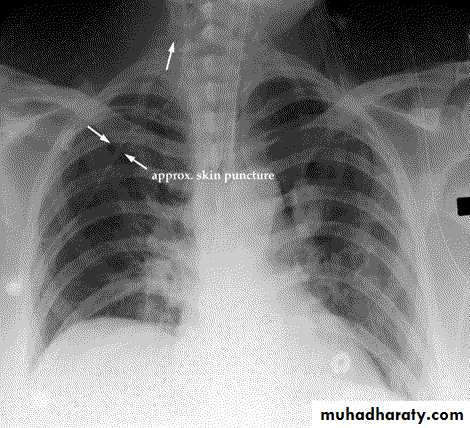

Open pneumothorax

Defect in chest wall provides a direct communication between the pleural space and the environmentLung collapse and paroxysmal shifting of mediastinum with each respiratory effort ± tension pneumothorax

“Sucking chest wound”

Rx: ABCs…closure of wound…chest drain